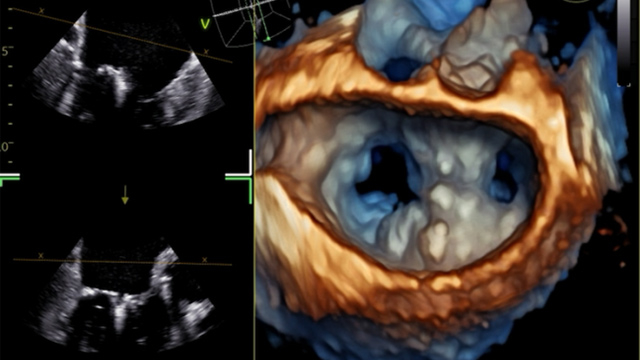

Transcatheter solutions for failed mitral TEER

This session presents innovative transcatheter solutions for managing failed mitral TEER procedures. It highlights advanced closure strategies for inter-clip mitral regurgitation, percutaneous approaches for recurrent mitral regurgitation, novel chordae tendineae replacement techniques, and potential bailout strategies including atrial flow regulation implantation for recurrent heart failure.